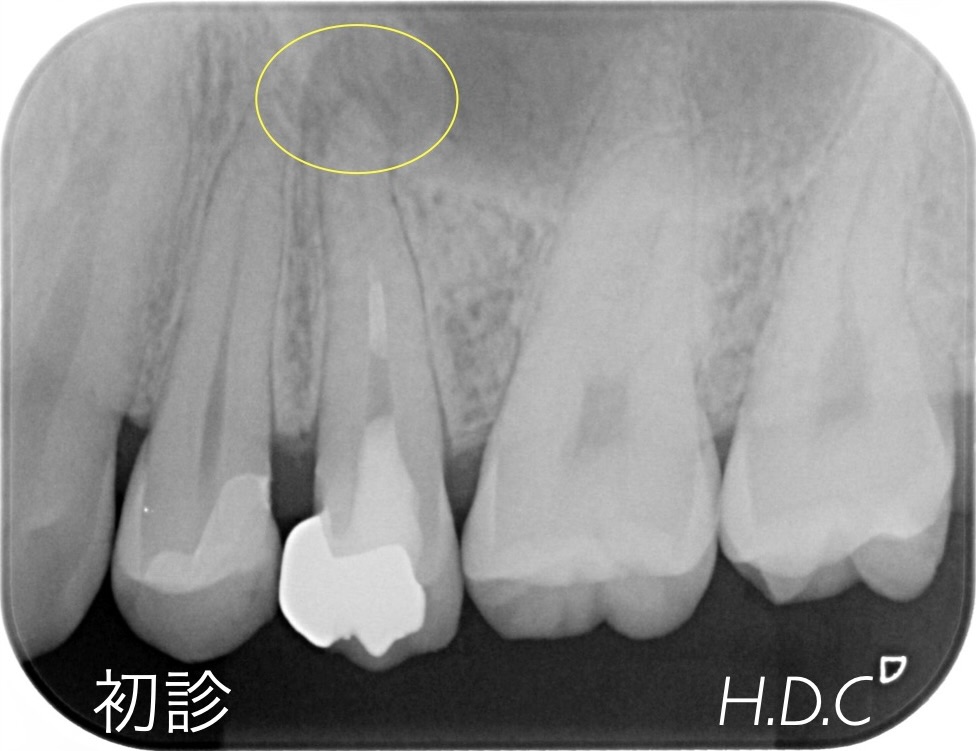

歯周病治療例③

(GTR法による再生治療症例)

- 年齢・性別

- 30代 女性

- 主訴

- 上の前歯がグラグラする。

- 診断名

- 重度歯周病(広汎型慢性歯周炎 Stage Ⅲ Grade B)

- 治療内容

- 他院で抜歯と診断された重度歯周病の上顎前歯に、歯周組織再生治療(GTR法)後、セラミック冠による補綴治療を行いました。

- 治療期間

- 約2年

- 治療費用

- 歯周外科治療(GTR法)保険診療(現在、当院ではGTR法は保険診療では行なっていません)補綴治療 ¥504,000 セラミック冠・ファイバーコア4本(2007年診療時)

- リスク

- 歯周組織再生療法時の出血・腫脹・青痣、歯肉退縮、セラミック冠の破折、脱離など